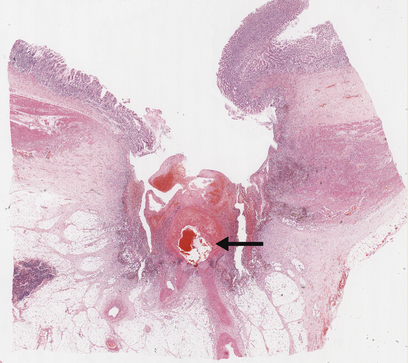

Chronic peptic ulcers (Fig. 15.9) seem to occur most frequently at mucosal junctions. Thus gastric ulcers are often found where antral meets body-type mucosa on the lesser curvature; duodenal ulcers are found in the proximal duodenum close to the pylorus; oesophageal peptic ulcers are found in the squamous epithelium just above the cardio-oesophageal junction; and stromal ulcers—those occurring following construction of a gastro-enterostomy linking stomach and jejunum—are found in the jejunal mucosa immediately adjacent to the gastric mucosa of the stromal margin. This suggests that ulceration is most likely to occur where acid and pepsin first come into contact with a susceptible mucosa.

image

Fig. 15.9 Chronic gastric ulcer. Histological section through the ulcer revealing a deep breach of the main muscle layers and haemorrhage around an artery (arrowed) in the ulcer base. The patient presented with a profuse haematemesis (vomiting blood) and underwent emergency partial gastrectomy.

Morphology

Grossly, chronic peptic ulcers are usually less than 20mm in diameter but they may be larger and can exceed 100mm in diameter. The edges are clear-cut and overhang the base. Microscopically, the base consists of necrotic tissue and polymorph exudate overlying inflamed granulation tissue which merges with mature fibrous (scar) tissue. The latter frequently occupies the remainder of the wall, with the muscularis propria completely replaced by fibrous tissue. Arteries within this fibrous base often show extreme narrowing of their lumina by intimal proliferation (endarteritis obliterans).

Ulcers heal by a combination of epithelial regeneration, which reconstitutes the mucosa, and progressive fibrosis. Later, shrinkage of the fibrous tissue (cicatrisation) may lead to pyloric stenosis or a central narrowing of the stomach, the so-called hour-glass deformity.

More immediate complications of peptic ulcers include:

perforation, giving rise to spillage of gastric contents into the peritoneal cavity and peritonitis

penetration, whereby the ulcer erodes into an adjacent organ such as the liver or pancreas

haemorrhage, from eroded vessels in the ulcer base (Fig. 15.9).